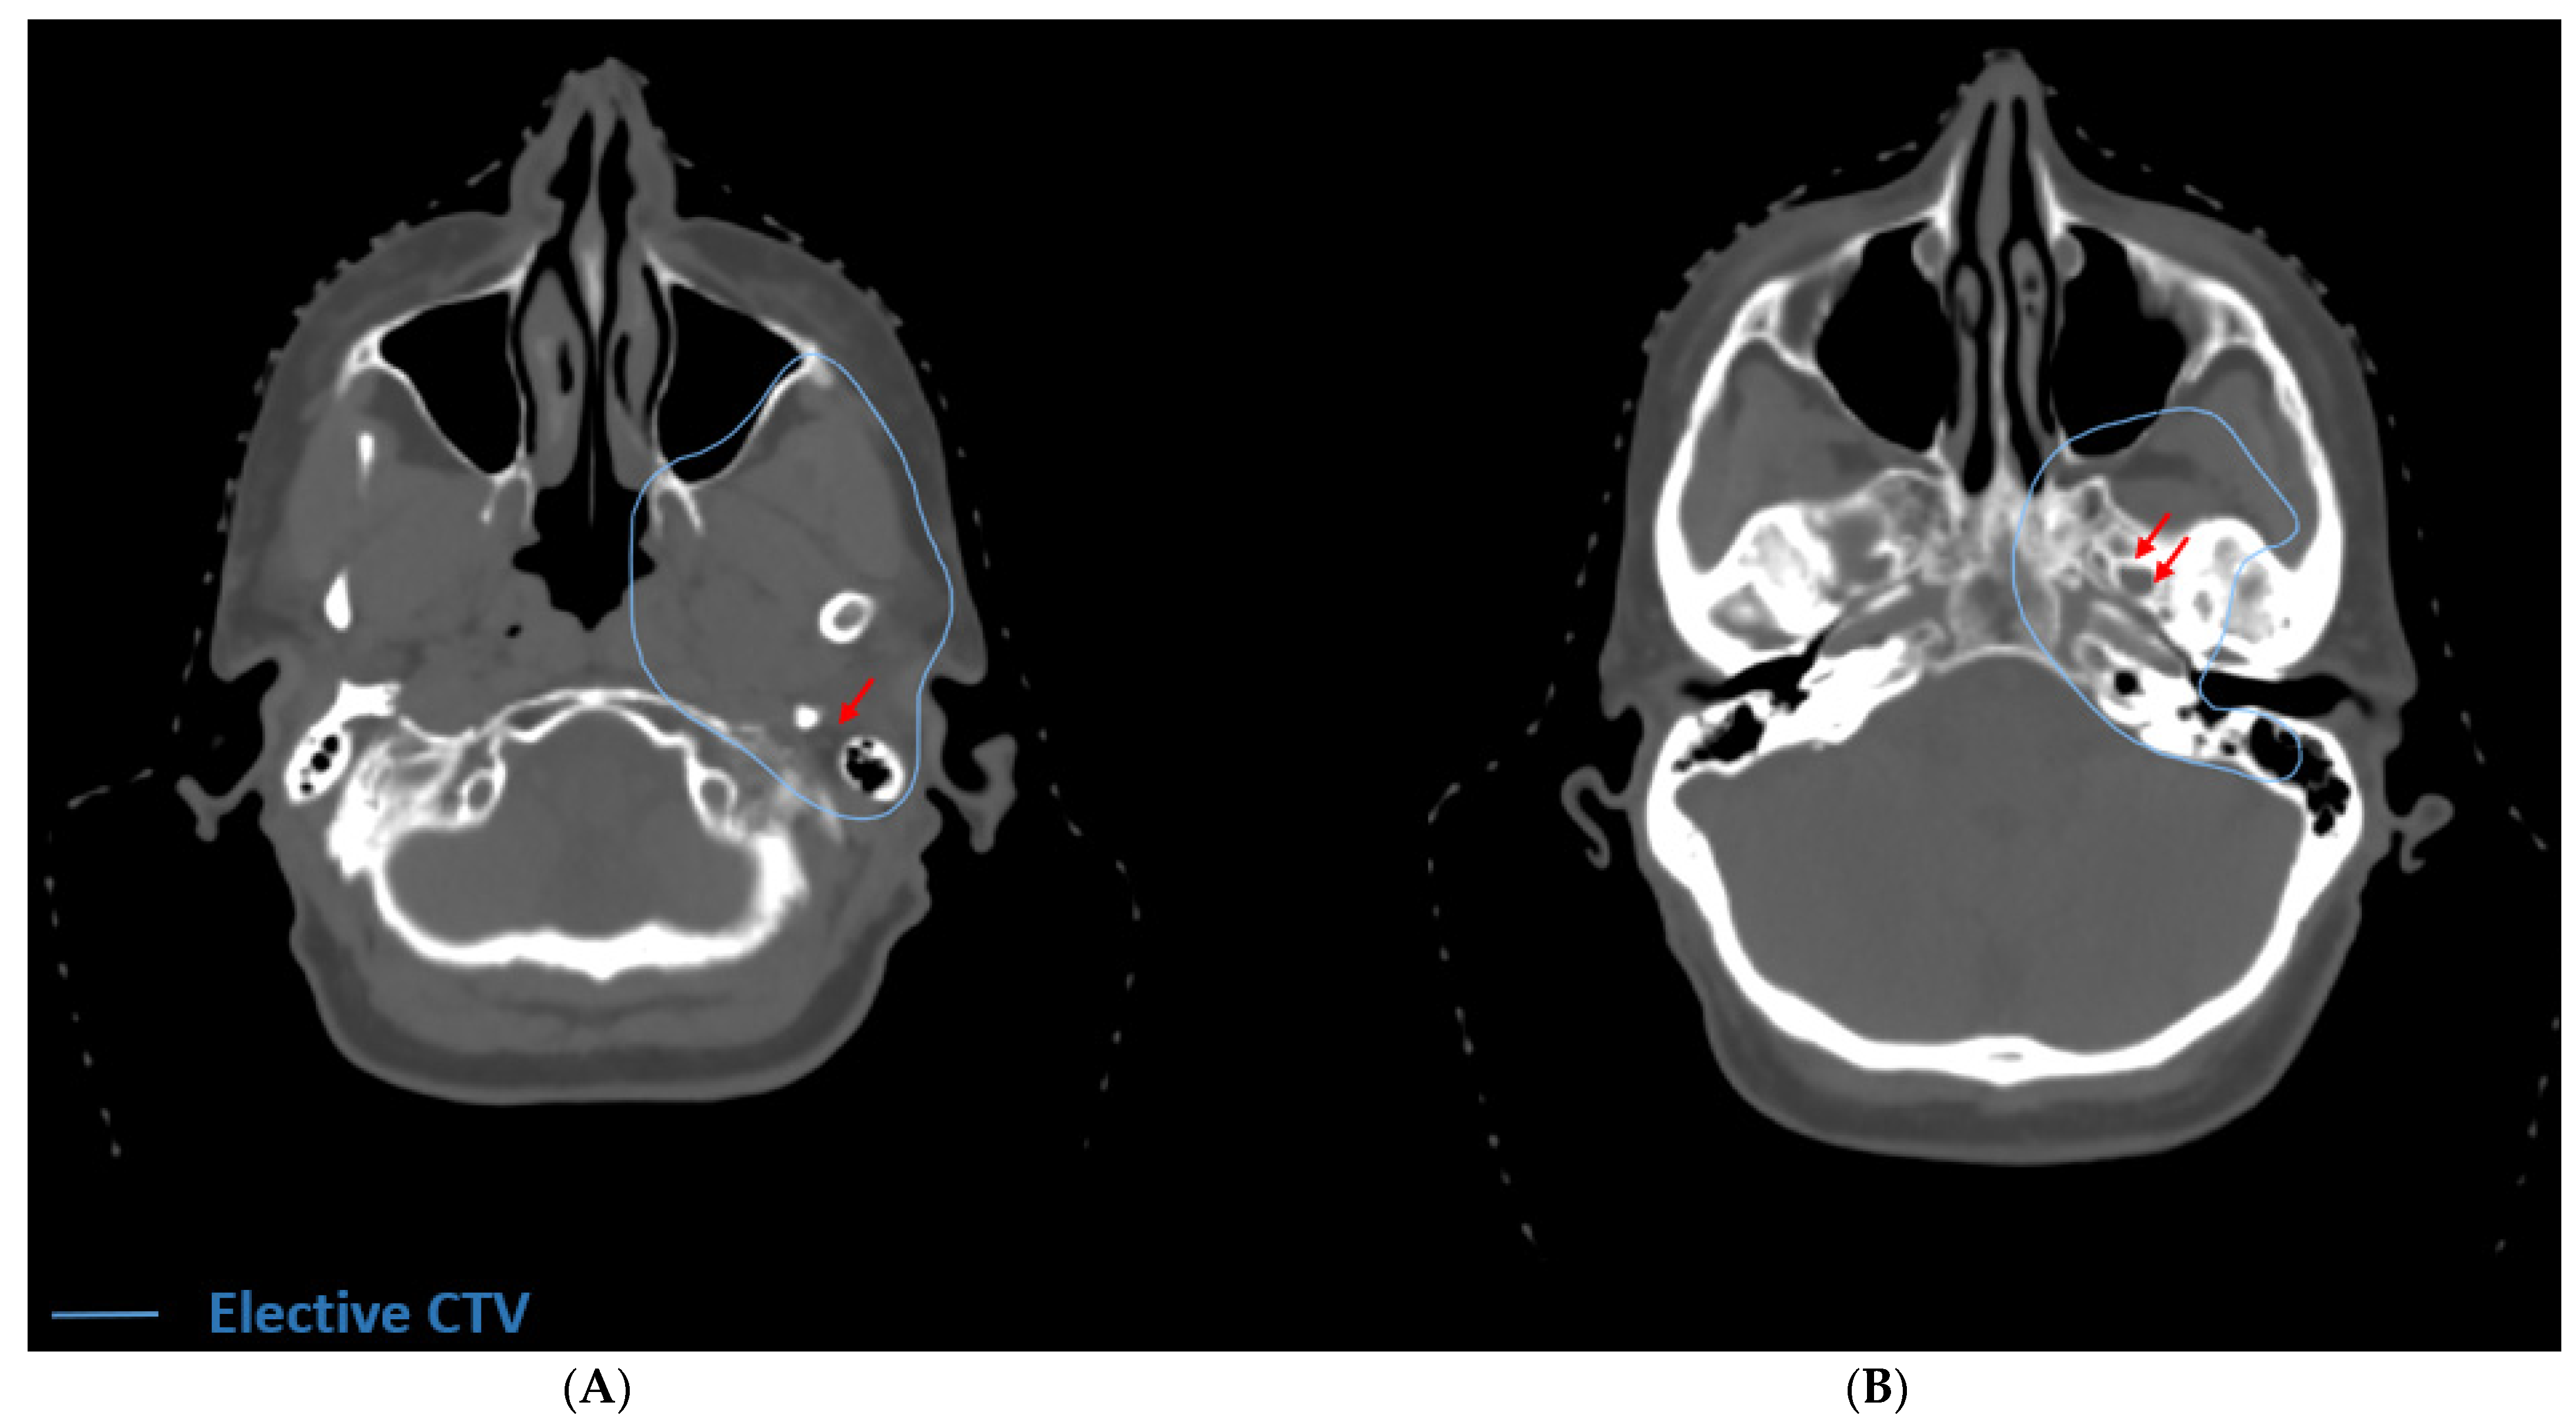

In all surgically resected cases of ACC in which adjuvant radiation therapy is warranted, the primary tumor bed should be covered. The decision of when to electively treat at-risk cranial nerve pathways is more complex. Tracing the CNs back to the base if skull is clinically challenging and can result in increased toxicity; thus it is prudent to consider the balance of potential benefit of elective CN pathway coverage against the toxicity of volume expansion. ACC usually warrants serious consideration of elective coverage of at-risk CN pathways innervating the primary tumor site due to its propensity for PNTS [32,33]. In rare cases of early stage (T1 or T2) ACC of a major salivary gland in which PNI is not observed, treatment of the primary tumor bed alone with margin should be considered. ACC rarely involves the lymphatics [34] and therefore the neck should not routinely be treated unless there is histologically confirmed disease in the neck or a high suspicion based on imaging. Advanced T-stage is associated with an increased risk of nodal involvement, and treatment of the neck can be considered in more advanced cases of this subtype [35]. We have outlined common clinical ACC cases representing a variety of head and neck cases with PNI/PNTS (Table 1). There are previously published contouring guidelines [36,37,38,39,40,41,42] to aid in the target delineation of relevant CN pathways. For ACC arising from the parotid gland with extensive PNI or frank tumor involvement along CN VII, we recommend electively covering the stylomastoid foramen and the proximal course of VII in the temporal bone (Figure 3A) [43,44]. By contrast, in cases of microscopic PNI in early-stage disease of the parotid gland, coverage should only include the stylomastoid foramen and the mastoid segments of VII with the cochlea spared. If there is concern for involvement of the auriculotemporal nerve, it and V3 are electively treated up to the foramen ovale (Figure 3B) [45].

Figure 3.

Definitive radiation for unresectable ACC of the deep lobe of the parotid with PNTS. (A) The elective volume includes the stylomastoid foramen (red arrow). In this case, there was extension into the parapharyngeal space and infratemporal fossa. (B) The elective volume includes the foramen ovale (double red arrows) because of radiographic involvement of V3. In this case the elective volume was treated to 56 Gy.